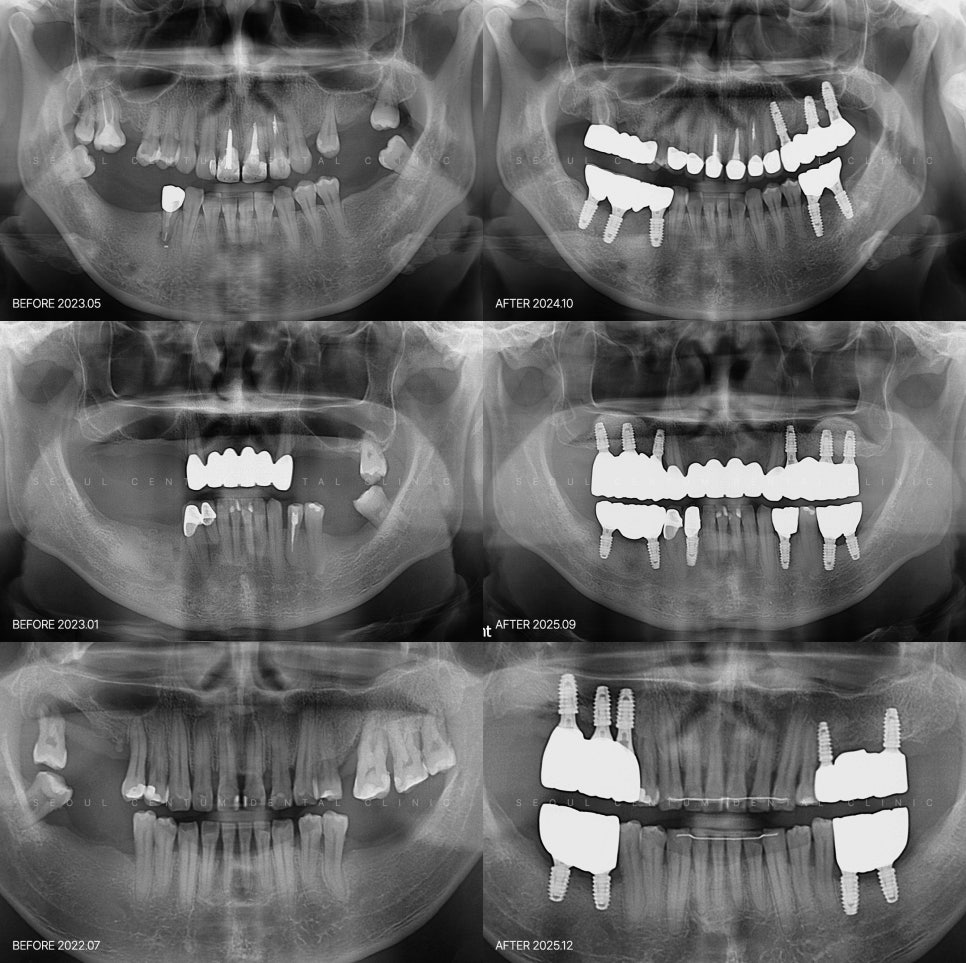

여러 개의 스크류를 식립한 뒤

그 위에 어버트먼트와 보철물을 순서대로 연결해

기능을 회복하는 방식인데요.

과거보다 더 정밀한 구조 설계를 바탕으로

효율적인 진행이 이뤄지고 있습니다.

모든 자리에 임플란트를 식립하지 않고

6~10개 정도만 식립해서

보철물을 연결하는 치료 방식,

일명 브릿지(Bridge)도 널리 사용되는데요.

턱뼈와 하중 분산 구조를 고려한 설계로

적은 개수만으로도 충분한 안정성을

확보할 수 있기 때문입니다.